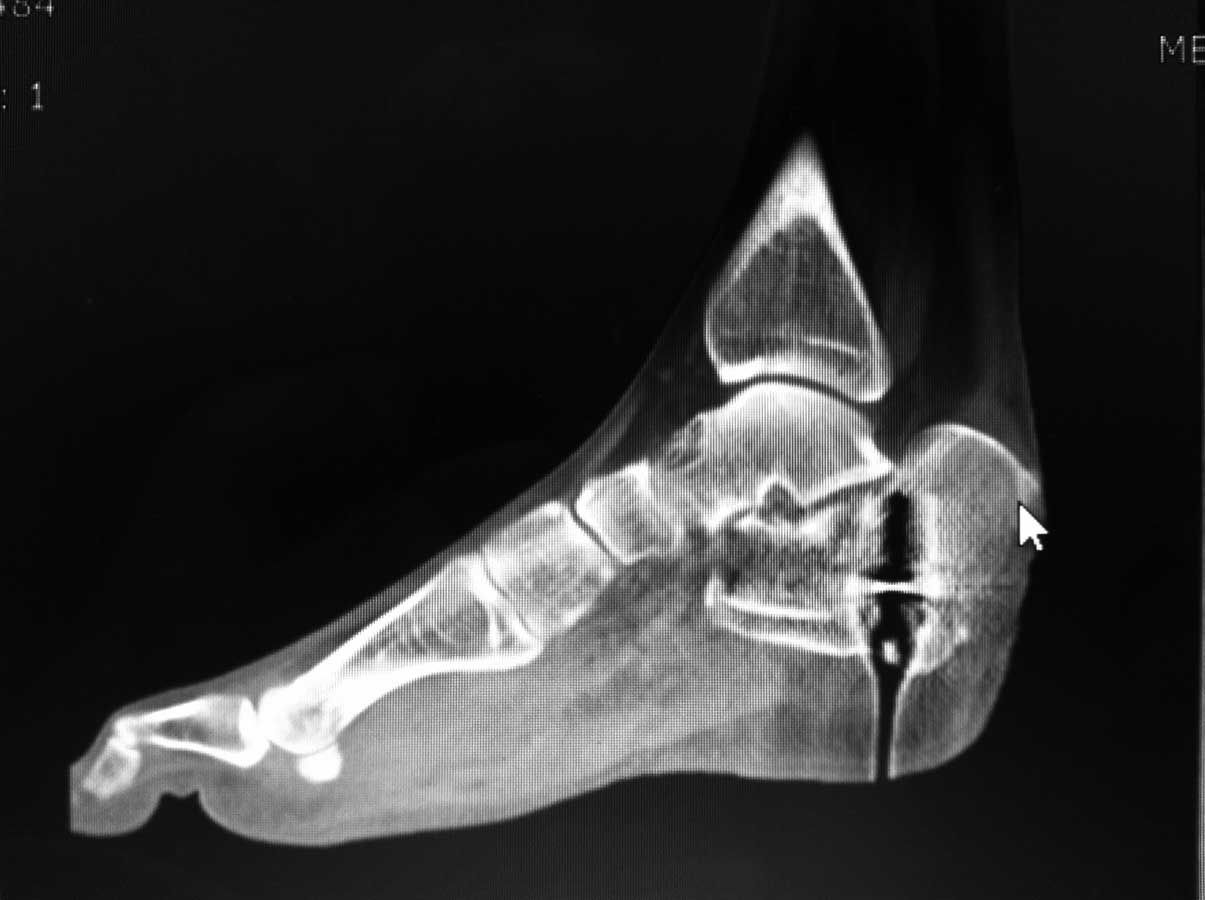

Даже на данном снимке можно . понять что перелом оскольчатый, внутрисуставной и захватывает заднюю и переднюю фасеты по крайней мере. Я тоже начал бы растягивать на аппарате (спицы спереди и сзади), но добавил бы locking plate открыто если больной кооперирующий и не курит. КТ нужна. Goodluck . Аарон

немного КТ

На аппарате к сожалению не возможно провести репазицию отломков при оскольчатых переломах пятки. Единственное что вы добетесь это востановите свод стопы. Так как поциент молодой я всётаки склонен к открытому методу используя специальную пластину. Во время операции будте внимательны к мягким тканям.